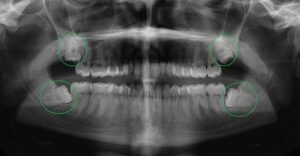

- Khám và Tư Vấn: Trước khi tiến hành nhổ răng khôn, bác sĩ sẽ thăm khám và đánh giá tình trạng răng miệng của bạn. Các bác sĩ sẽ chụp X-quang để xác định vị trí và hình dáng của răng khôn, từ đó đưa ra phương án điều trị hợp lý.